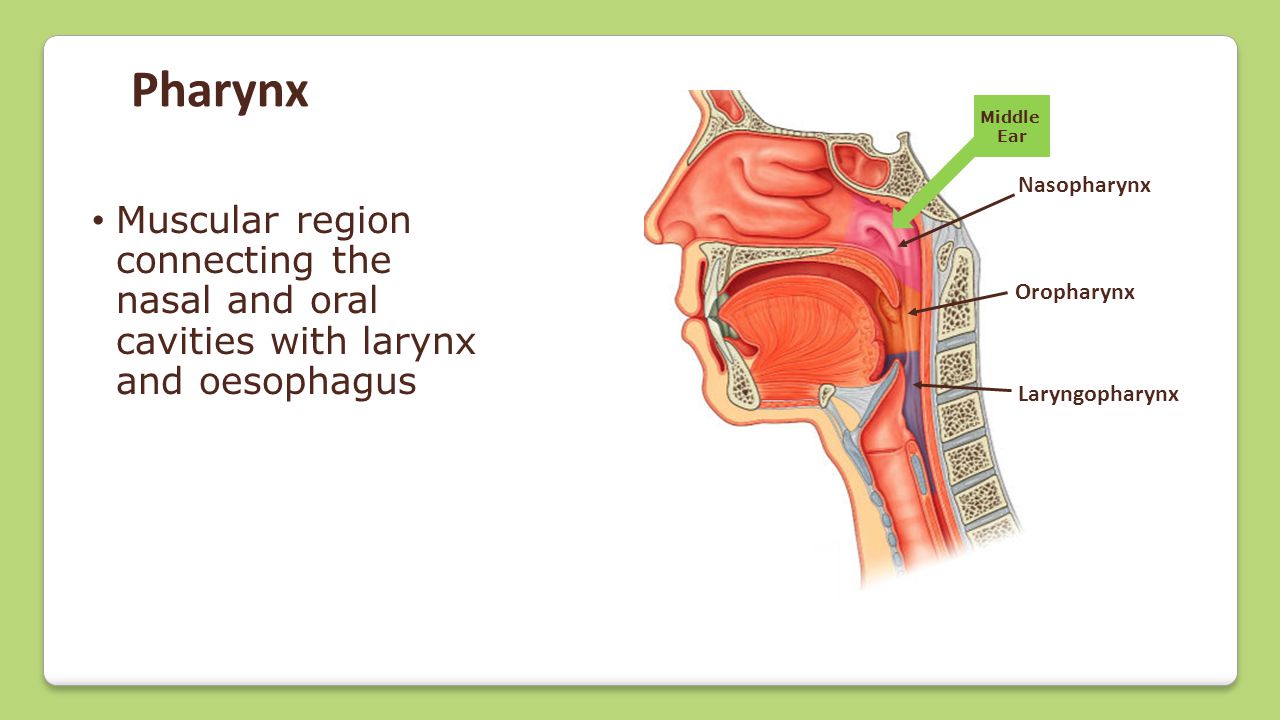

(2) Pharynx:

The nostrils lead into the pharynx which is the lower end of the mouth cavity.

(3) Larynx:

The pharynx leads into the larynx which is also called the voice box. The larynx leads into the trachea, which is also called the wind pipe.

(2) Pharynx:

The nostrils lead into the pharynx which is the lower end of the mouth cavity.

(3) Larynx:

The pharynx leads into the larynx which is also called the voice box. The larynx leads into the trachea, which is also called the wind pipe.